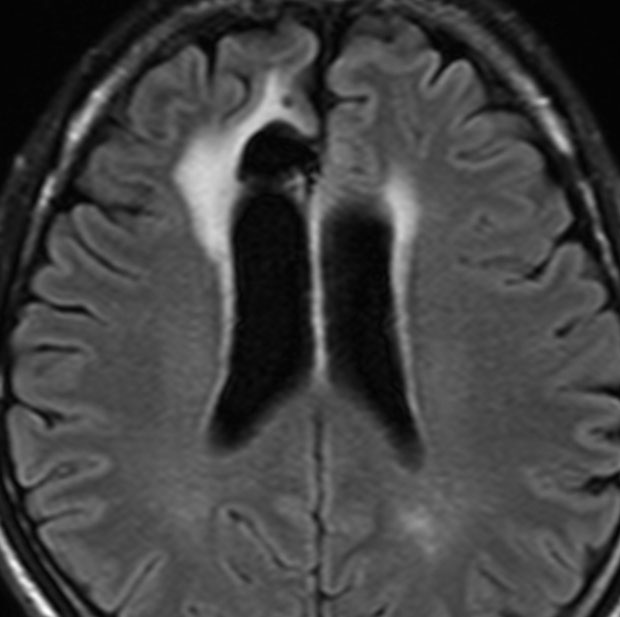

3歳の子どもの髄芽腫の放射線治療後に生じた脳萎縮

3歳の髄芽腫です。発症時から小脳表面や小脳橋角部を含めて転移がありました stage M2。化学療法で腫瘍はかなり縮小して,3歳7ヶ月まで頑張ってから,後頭窩照射 25.2グレイ14分割と脳脊髄照射 CSI 28.8グレイ16分割の放射線治療をしました。当時このような例では,脳脊髄照射 36グレイが標準治療でしたから,これでもかなり線量を落としました。

左側の画像は照射後4ヶ月目です。延髄の左側に放射線壊死が生じました。これは数ヶ月かかってゆっくり消褪しました。右側の画像は照射後1年くらいのものです。大脳白質にびまん性に萎縮性変化がみられます。典型的な放射線治療による白質萎縮です。この程度の線量でも脳壊死や全脳萎縮を生じない子どももいます。

放射線の副作用は同じ線量でも個人差がとても大きいです idiosyncrasy